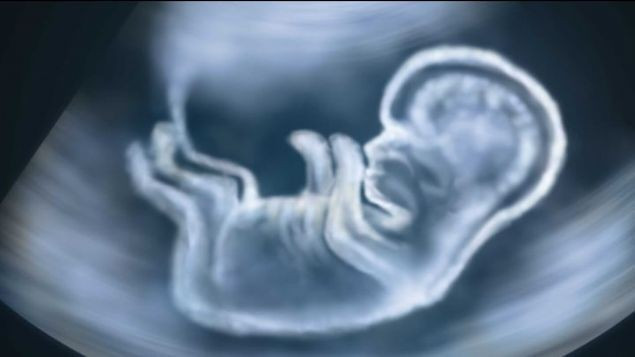

Bir insan embriyosunun, gelecekte ani ölüme neden olan ve sık görülen bir kalp hastalığını tetikleyen genlere sahip olduğu saptanmıştı.